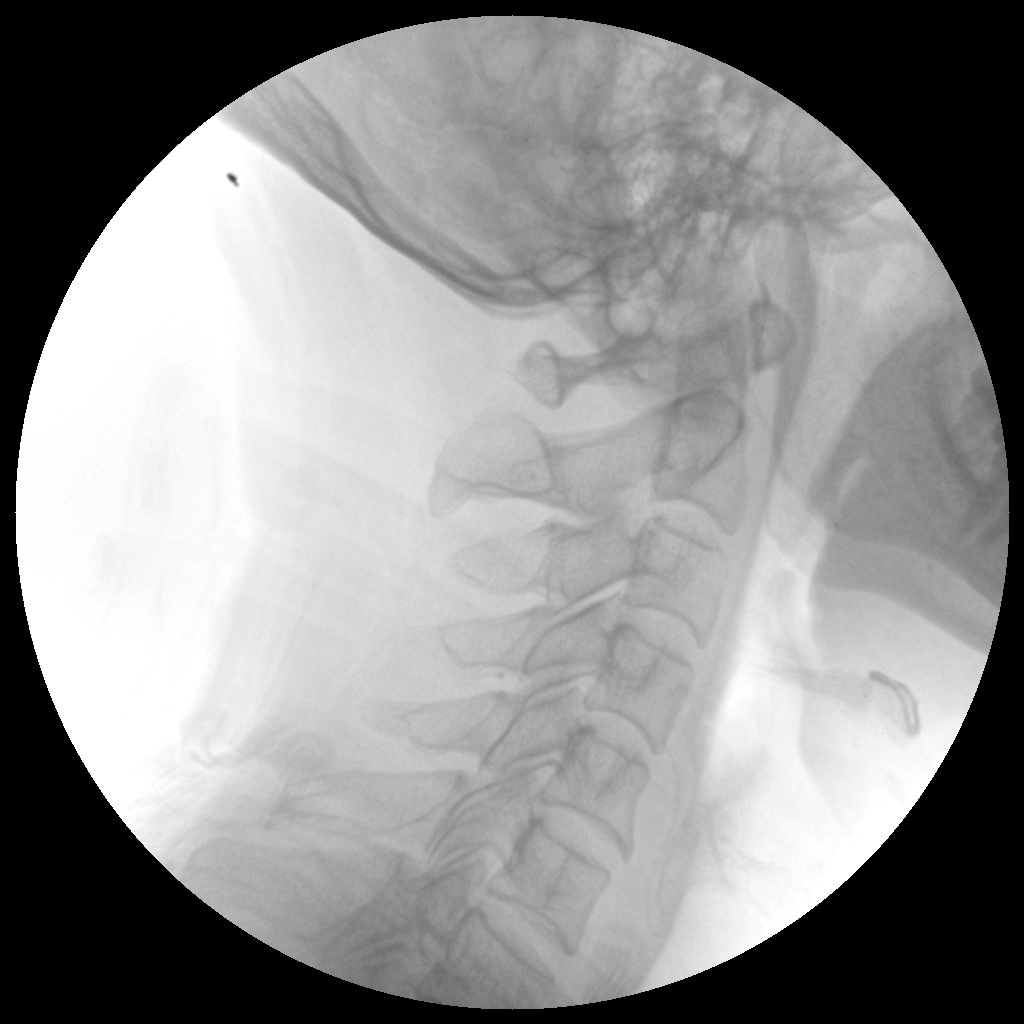

PLX112B 系列高频移动式手术X射线机

●经典影像工作站,可隔室操作避免辐射●全数字化百万像素影像系统,图像清晰●灵活的C臂机架设计,满足临床大范围运动●临床功能丰富,具备脉冲控制、数字摄影、自动透视等●具备手持控制器,远离主机也可自由控制